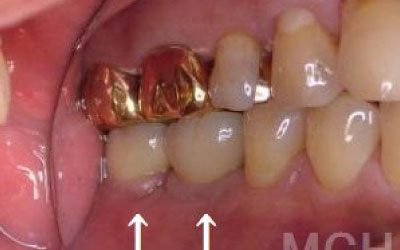

「お口の状態や噛み合わせによって異なるため一概には言えませんが、一般的には奥歯が適しています。

特に、一番奥の歯とその隣の二番目の奥歯が重要です。

噛み合わせの力の60%以上がこの2本の奥歯で支えられているため、ここをしっかりとインプラントで治療するのが理想的です。

インプラントの利点は、入れ歯のように取り外す必要がなく、ご自身の歯のように自然に噛める点です。

そして最大の利点は、周囲の歯の寿命を短くしないことです。

ブリッジや入れ歯では、他の歯に負担がかかり、歯が連鎖的に抜けていくことがあります。

しかし、インプラントは周囲の歯に一切負担をかけないため、残った歯にとって最も優しい治療法です。